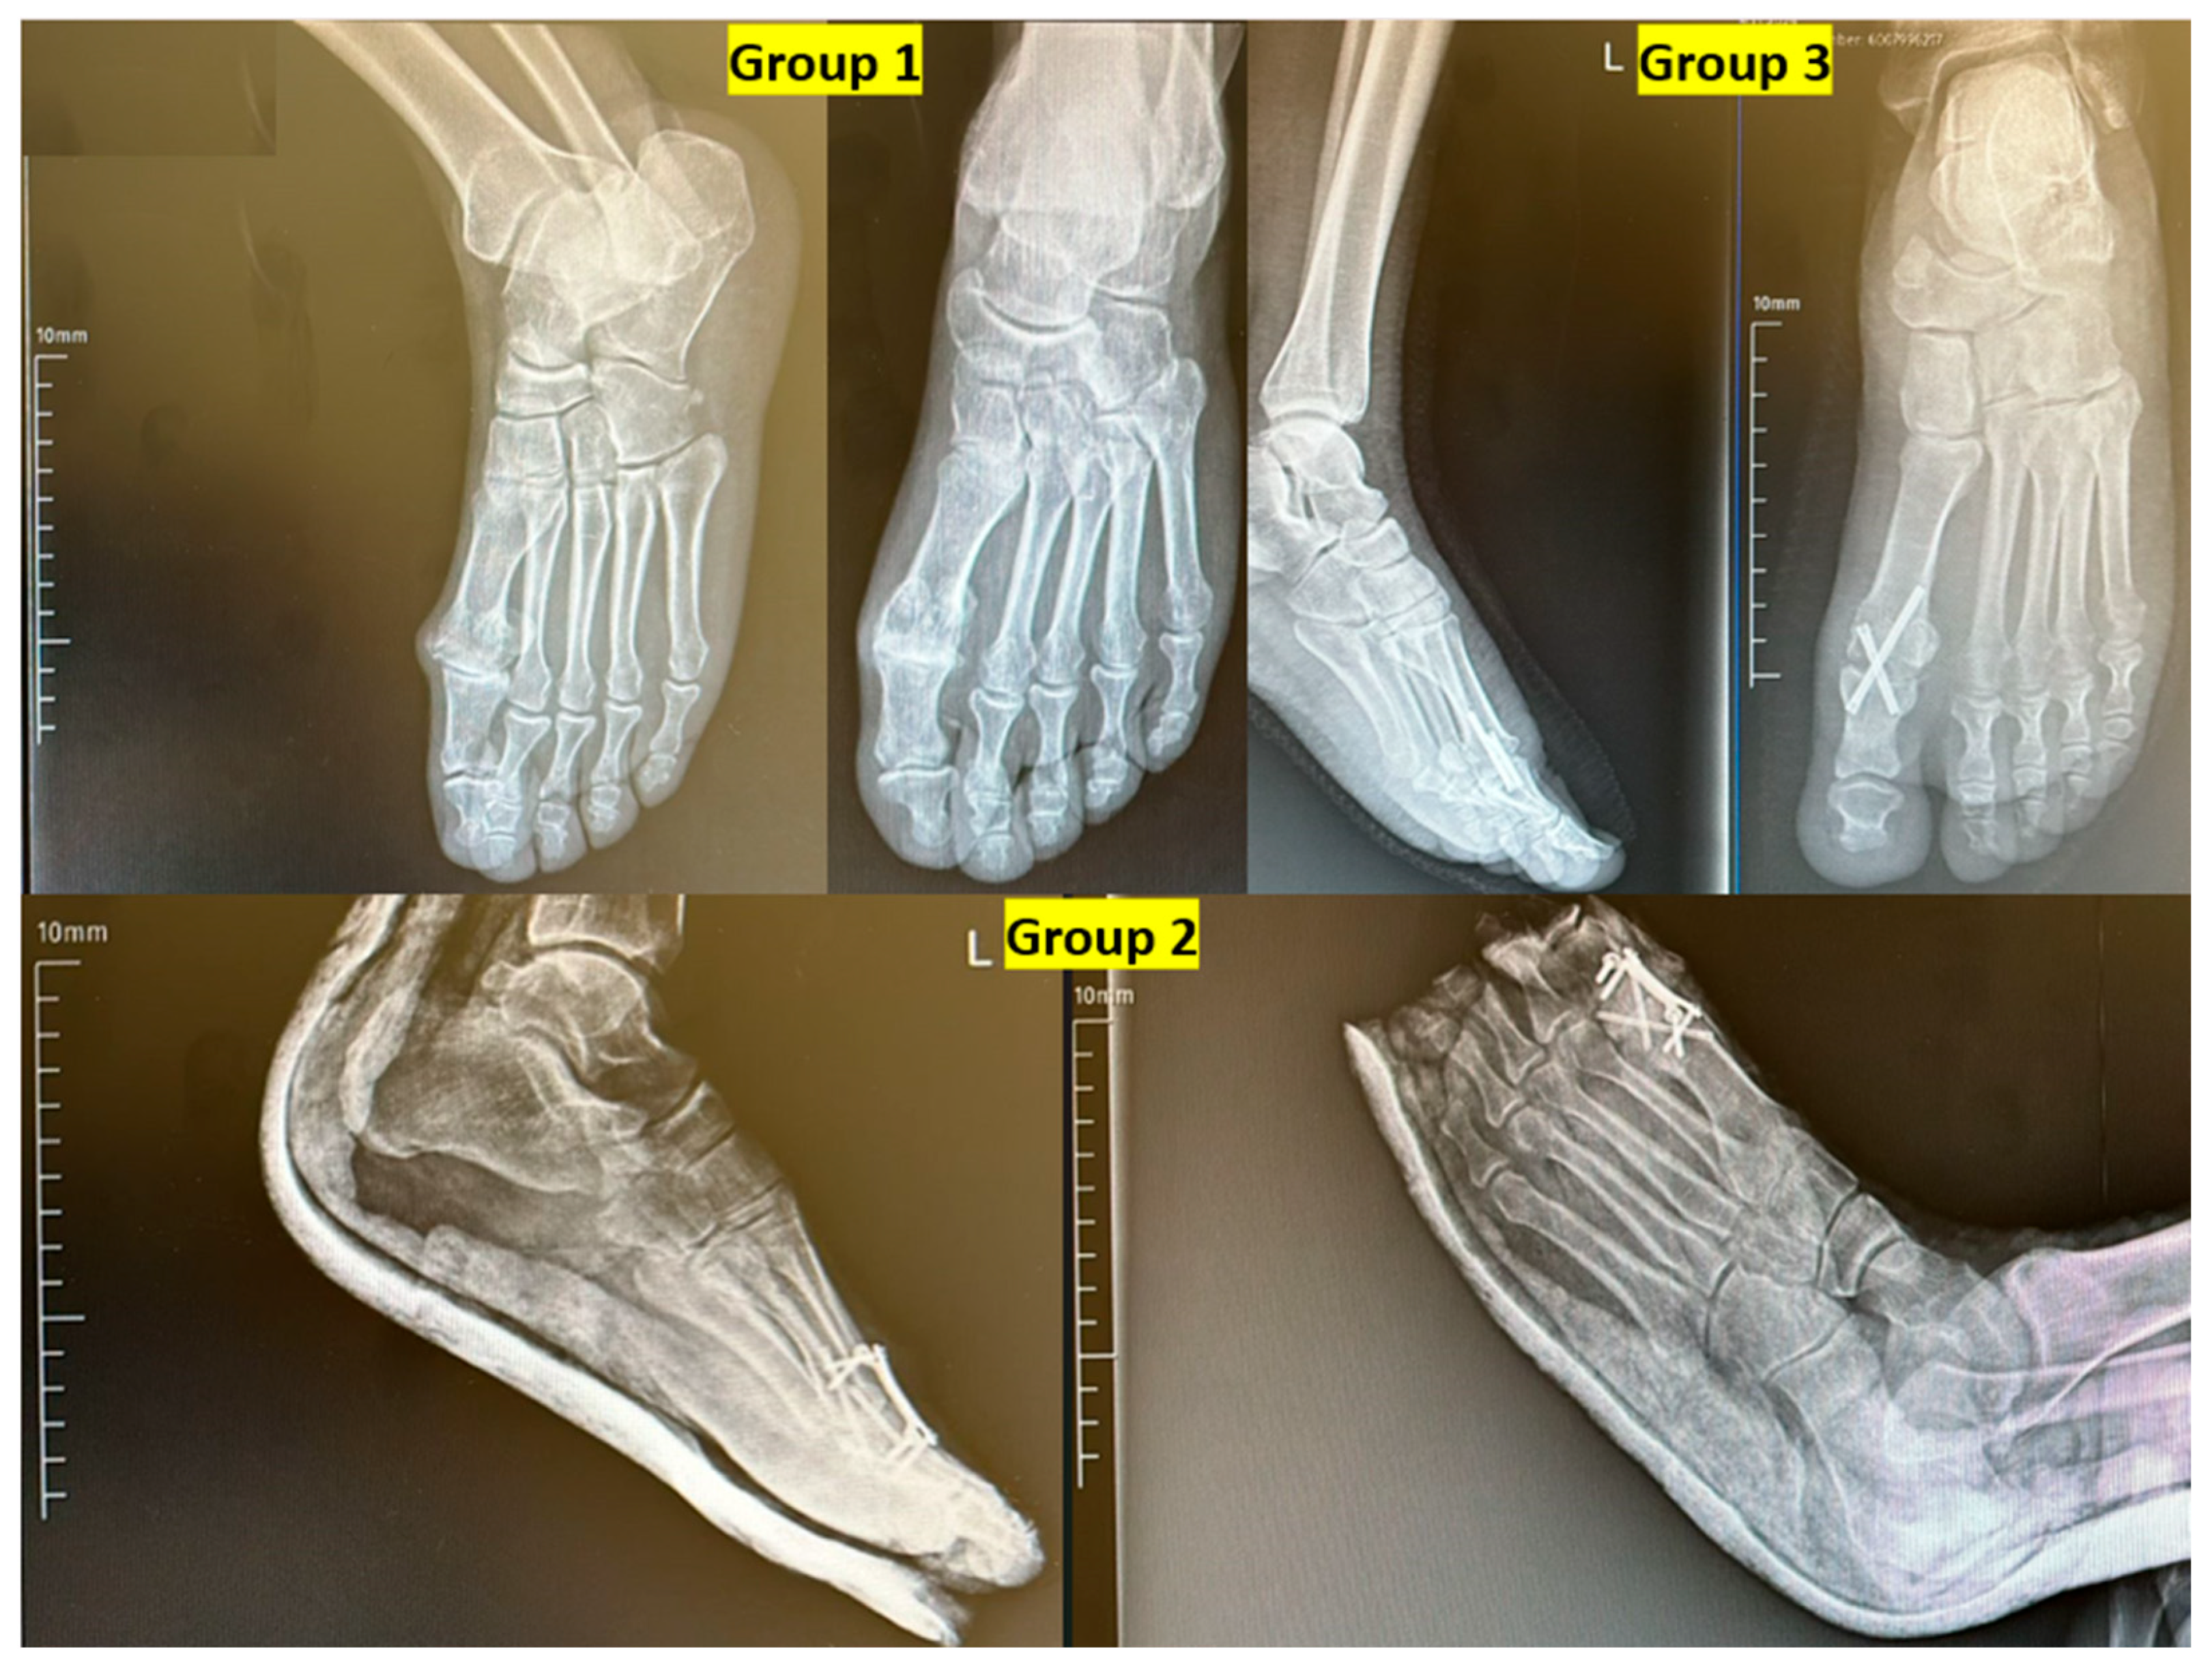

While dorsiflexion angles in Group 2 remained within the accepted normal range (15.9–26.9°), the values were significantly lower compared to Group 1, where angles exceeded the average upper limit. This difference was statistically significant (p = 0.04) (Figure 5).

While dorsiflexion angles in Group 2 remained within the accepted normal range (15.9–26.9°), the values were significantly lower compared to Group 1, where angles exceeded the average upper limit. This difference was statistically significant (p = 0.04) (Figure 6).

A lateral radiographic view demonstrating the arthrodesis angle is shown in Figure 6. The image illustrates proper alignment of the first toe with approximately 10–15° of dorsiflexion, which is considered the ideal postoperative fusion position for restoring gait mechanics and ensuring optimal functional outcomes (Figure 7).

In the present study, the normal range for first toe dorsiflexion was considered to be approximately 15.9–26.9 degrees [15]. While dorsiflexion angles in Group 2 remained within this physiological range, the values were significantly lower than those in Group 1, where the angles tended to exceed the upper limit of the normal range. This difference was found to be statistically significant. Although the difference in dorsiflexion angle between groups reached statistical significance, all values remained within the accepted physiological range (15–30°). Thus, while statistically notable, this difference is unlikely to have meaningful clinical implications in terms of gait mechanics or functional recovery. This highlights the importance of distinguishing statistical significance from clinical relevance in interpreting our results.

Previous studies have suggested that the optimal arthrodesis position for the first MTP joint includes approximately 10–20° of valgus and 10–15° of dorsiflexion [22,23]. However, a study by Van Doeselaar et al. reported no clear association between fusion angles and functional outcomes [24]. In contrast, our findings indicate that Group 2 achieved fusion angles closest to the recommended alignment. When these radiographic findings are considered alongside the superior functional scores observed in this group, it suggests that proper arthrodesis positioning may positively influence postoperative functional outcomes.

Figure 7. Lateral radiographic view demonstrating optimal dorsiflexion angle following first metatarsophalangeal (MTP) joint arthrodesis. L: Left.